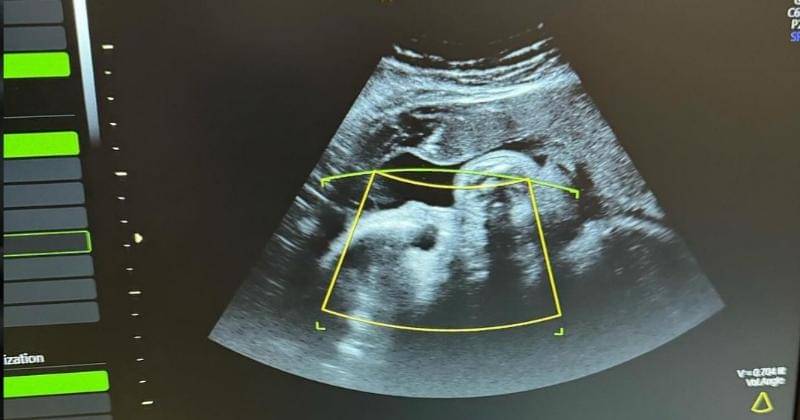

Atta pun mengunggah foto saat Aurel melakukan pemeriksaan USG sembari mengelus perut istrinya tersebut. Ia mengharapkan kesehatan untuk Aurel menjelang persalinan.

"2 minggu lagi kita ketemu ya nak.. Sehat2 mama.. 🤍," tulis Atta dalam unggahannya.